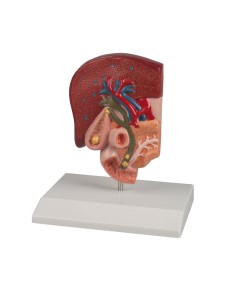

Modèle de maladie de l'articulation de la hanche 3B Scientific 1019506